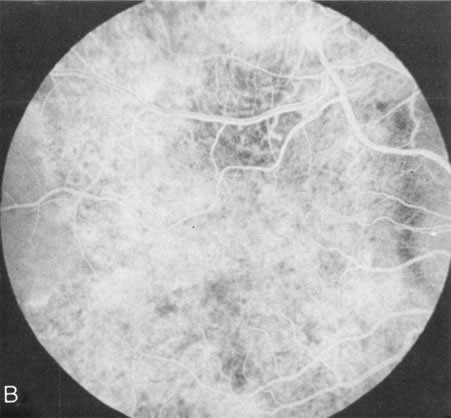

Fundus albipunctatus typically shows multiple, small white dots, which are deep in the retina, regular, and monotonous in their similar size, shape, and color and which involve the entire posterior pole into the equator while sparing the macula (Fig. 3A). These multiple dots are not apparent on FA. There may be a mottling of the background choroidal fluorescence and small areas of irregular transmission hyperfluorescence (especially surrounding the macula), but neither of these findings corresponds to the observed white dots8,9 (Fig. 3B).

Fig. 3. Fundus albipunctatus. The few small transmission defects on angiography (A) do not correspond to the multiple small white dots that are characteristic of this disease (B).